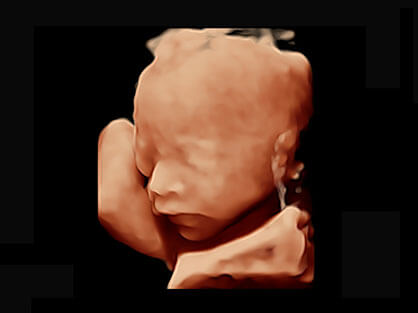

0.5mm厚度的薄层切片显像,可清晰显示微小病灶的连续断面。

可同时显示组织结构表面和内部的轮廓信息,达到透视效果,为临床提供更丰富的诊断信息。